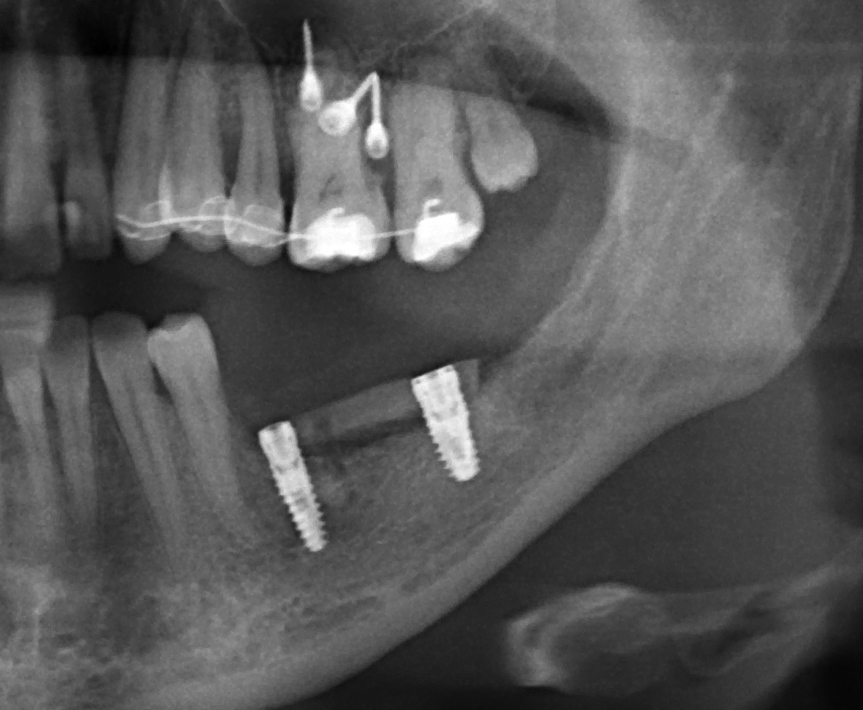

Казалось бы, всё просто - готовится лунка в кости, вкручивается имплантат, после интеграции которого, фиксируется коронка. На самом деле, процесс имплантации несколько сложнее и интереснее. Сейчас я покажу его вас от старта до финиша и постараюсь объяснить некоторые наиболее важные моменты.

27.01.2018Станислав Васильев